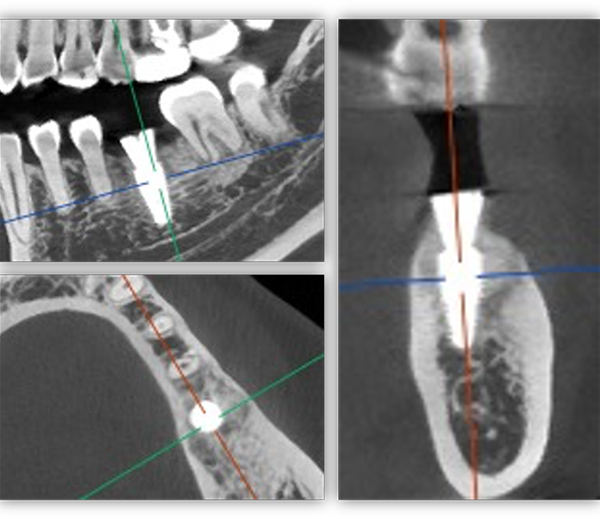

6號牙也就是第一磨牙,是最早萌出的恒牙,比較容易齲壞。它雖然不在前牙美學區,不太容易影響容貌,但出于對美學的高要求,我在設計方案時也考慮了是按常規流程先拔牙,再備洞,還是以修復為導向,先按現有的牙冠來確定未來修復體的形狀,再去反推種植體植入的位置。后者對醫生來說難度更高一些,但更有利于復原天然牙的形態。

為保證這個方案的順利實施,我通過查閱文獻去印證方案的可行性,還為她建議了適合的種植體,原來三個月的骨結合時間能縮短為兩個月,種植體功不可沒。